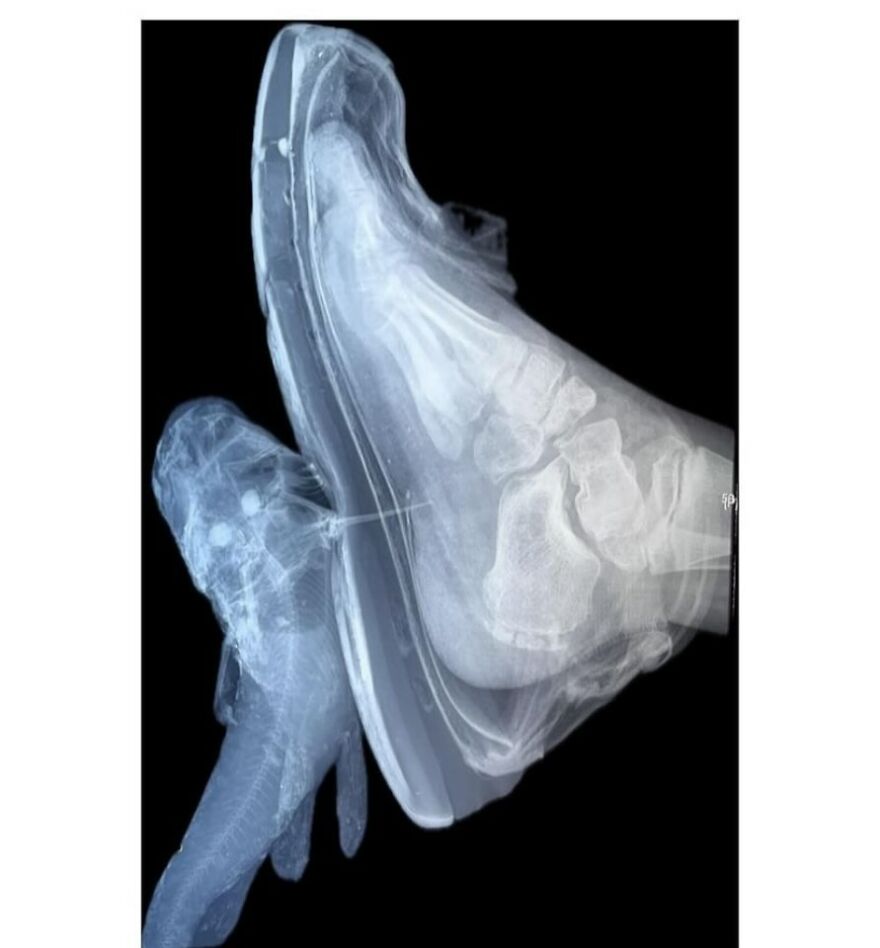

Foot binding (also known as Lotus foot) was the custom of applying tight binding to the feet of young girls to modify the shape and size of their feet

It was practised in China from the Song dynasty until the early 20th century, and bound feet were considered a status symbol as well as a mark of beauty

Foot binding limited the mobility of women, and resulted in lifelong disabilities for most of its subjects, although some women with bound feet working outdoors have also been reported

The age in which the binding happens differs in areas, but happend between 4 and 8 years old. The process takes about two years and is extremely painful: bones in the foot are broken, and replaced under the foot. All this time, girls must keep walking to put pressure on the bind foot, and achieve the ideal shape and length. 1 in 10 girls would die during the binding because of complications, and other complications happend quite regurlaly: not all binded woman could walk properly because of binding gone wrong. The ideal length of a bound foot would be around 7 cm. Kind of the size of a thumb. Without bound feet woman were unmarriable. Woman with unbound feet often became maids or worse. Source: my head, because of books I've read. Edit: grammar mistake